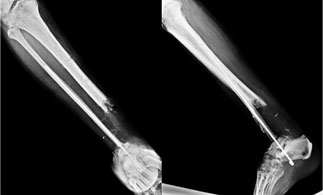

The xrays after 1 week of debridement and VAC dressing. The xray on the left side is as seen from the front (AP view) and the one on the right is as seen from the side (Lateral view)